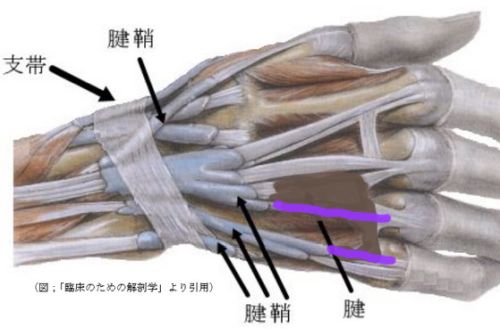

次の絵で分かるように薬指の腱は2本とも切れていたためだ。

2回の手術とも部分麻酔を希望して行いました。 なので手術中の医師の会話は聞こえます。 一回目の手術は、若手医師で相談しながら行ってました。研究資 料取りを了解してたのでビデオやカメラで撮影しながら行ってました。 あれ、腱って2本づつあるんだとか心配になるような会話も聞こえます。